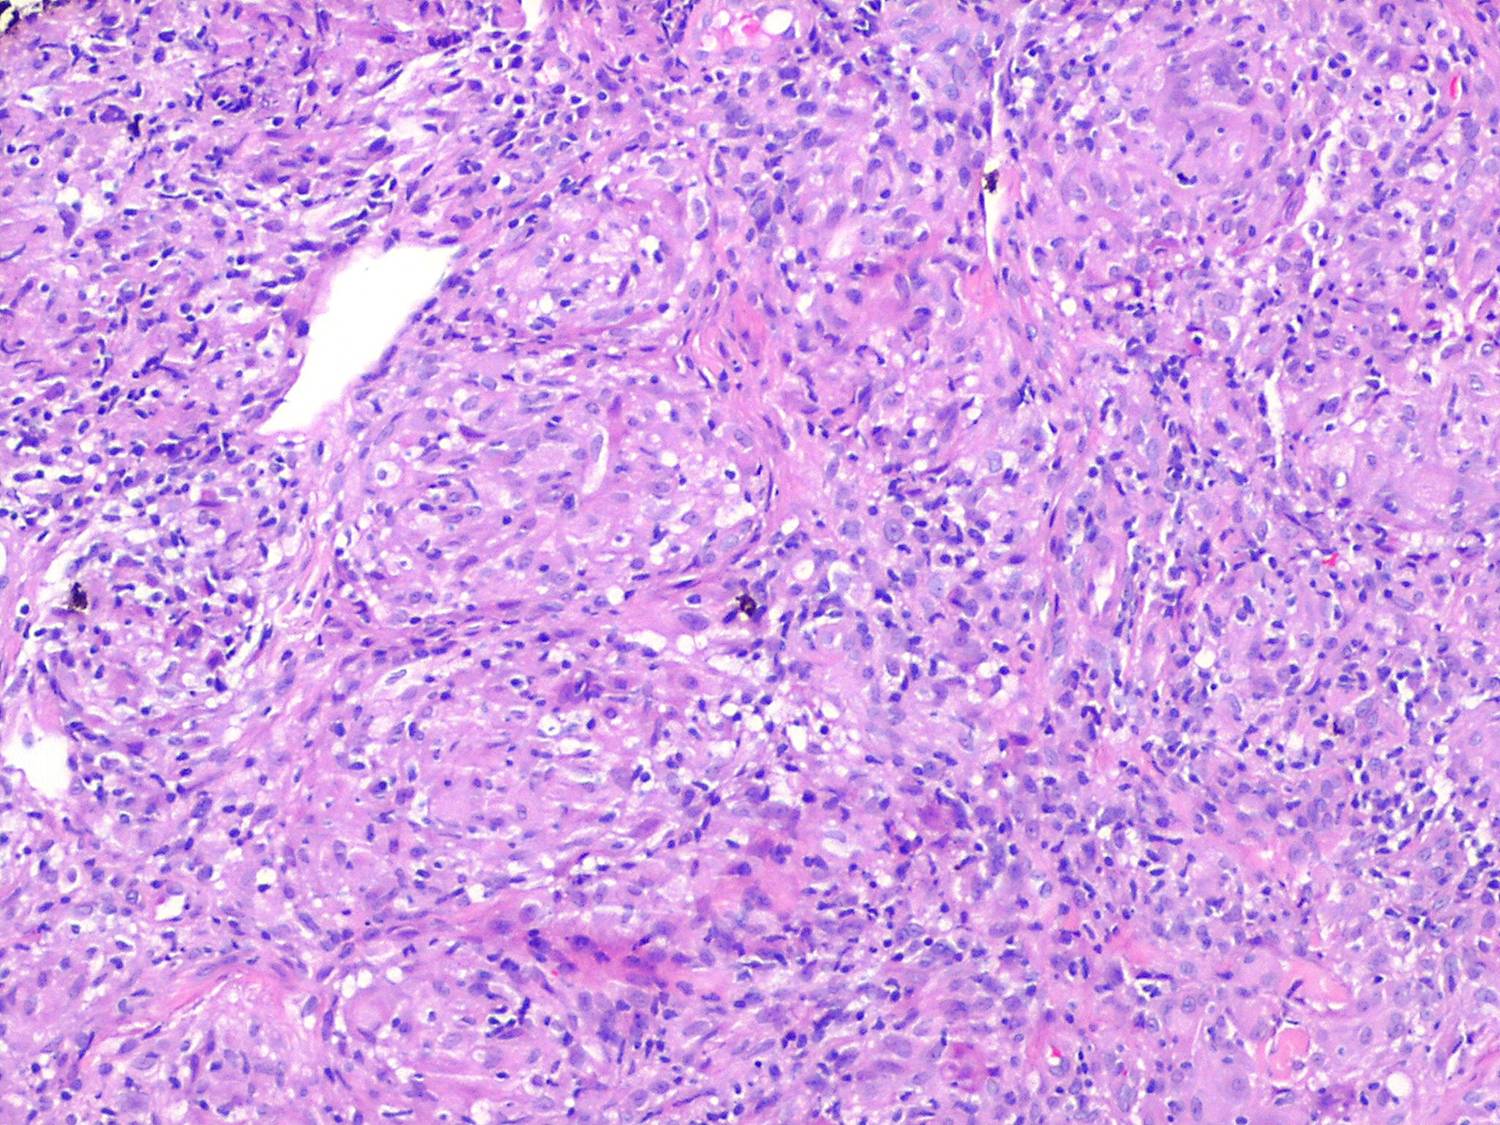

In typical cutaneous lesions of sarcoidosis, the well-demarcated islands of epithelioid cells contain few, if any, giant cells. Those that are present are usually of the Langhans type. A moderate number of giant cells can be found in old lesions. These giant cells may be large and irregular in shape. In a minority of cases, giant cells contain asteroid bodies or Schaumann bodies . Asteroid bodies , which are more common, are star-shaped eosinophilic structures that, when stained with phosphotungstic acid-hematoxylin, produce a center that is brown-red with radiating blue spikes . Schaumann bodies are round or oval, laminated, and calcified, especially at their periphery. They stain dark blue because of the presence of calcium. Neither of these two bodies is specific for sarcoidosis: They have been observed in a variety of other granulomas, including those of leprosy, tuberculosis, foreign-body reactions, and necrobiotic xanthogranuloma .

Classically, sarcoid has been associated with only a sparse lymphocytic infiltrate, particularly at the margins of the epithelioid cell granulomas . Because of the scarcity of lymphocytes, the granulomas have been referred to as “naked” tubercles. However, lymphocytic infiltrates in sarcoid may occasionally be dense, as in tuberculosis . Occasionally, small foci of fibrin or necrosis showing

eosinophilic staining is found in the center of some of the granulomas . A reticulum stain of sarcoid reveals a network of reticulum fibers surrounding and permeating the epithelioid cell granulomas. If the granulomas of sarcoidosis involute, fibrosis extends from the periphery toward the center, with gradual disappearance of the epithelioid cells . Fibrosis, however, is minimal to absent in most examples of sarcoidosis, with the exception of the morpheaform variant, where it is prominent {191}. Other features that may sometimes be seen include elastophagocytosis, increased dermal mucin, and lichenoid inflammation .